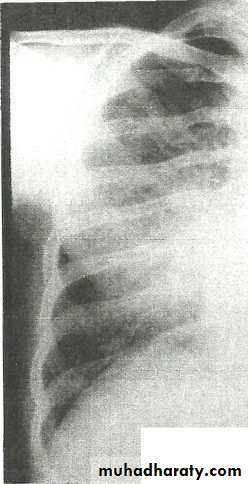

• Right lower lobe consolidation - Lat.

• The density lies posterior to fthe oblique issure- the position of the lower lobe.